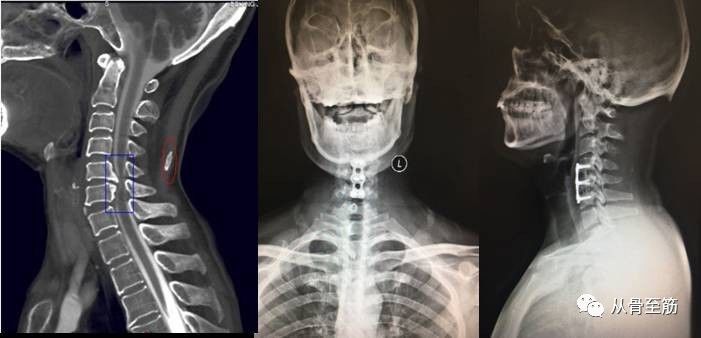

? ? ?一些在特殊的部位骨质增生,到一定程度后确实引起的疼痛、活动受限等临床症状,给我们带来了痛苦,此时称之为骨质增生症。在脊柱前方且增生较大者有时会对脊柱前方的食管、血管、神经等组织造成压迫引起临床症状;在后方者可能会压迫脊髓、神经根等引起临床症状;在关节内者可能会造成关节疼痛、活动受限等,特别是以膝关节骨质增生多见;跟骨骨质增生即跟骨骨刺有时会严重影响了患者正常生活。骨质增生症是病,得治。

? ? 手术治疗:如果症状很重不能缓解,严重影响到日常生活,生活质量明显下降甚到生活难以自理,应考虑及时手术干预,具体手术方式需要听从专业正规医生的安排。